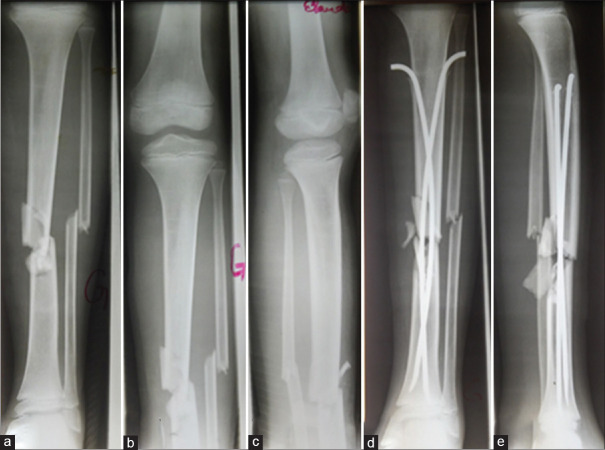

Results: Sixty-two patients underwent ESIN, of whom 44 patients (70.96%) were for femur fractures, nine patients (14.52%) for tibia and fibula fractures and nine patients (14.52%) for humerus fractures. The majority of the patients treated with ESIN were children older than 6 years. Nine patients (14.51%) and 13 patients (20.98%) underwent ESIN following polytrauma and multiple fractures, respectively. Seven patients (11.29%) were operated on through-closed ESIN method. The unavailability of image intensifier (38.71%) and the presence of bone callus (40.32%) were the major reasons for using the open ESIN method. Thirty-three patients (53.23%) had minor or major complications. The majority of patients had satisfactory therapeutic outcomes.

Conclusion: ESIN gives good results, even when the fracture site is approached.